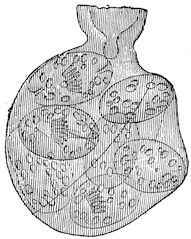

Fig. 5.—Head of a pig suffering from osseous cachexia.

Fig. 4.—Deformity of the face in the horse shown in Fig. 2.

The flat bones are particularly liable to this change, which is common to domesticated animals. The bones of the head are the first to suffer; later those of the pelvis. The lower jaw becomes swollen, particularly about the centre of the branches which may attain three, four, or five times, their normal thickness.

The depression in the submaxillary space disappears. The upper jaw undergoes similar changes, becoming deformed and thickened until the cavities of the sinuses and the hollow appearance of the palate are lost, while the face is so changed that it cannot be recognised as that of a horse, goat, etc.

The molar teeth are almost buried, their tables alone being visible at the bottom of a depression, the edges of which rise above the neighbouring parts (pig).

Mastication is clearly impossible, the jaws appear paralysed, the muscles powerless, and only swallowing is possible, a fact which explains why life is only prolonged to this stage in animals which can be fed with a spoon or bottle (pigs and goats). The bones of the cranium, although greatly changed in texture, are always less deformed than those of the face.

The changes are such that it is often easy with a mere post-mortem knife to cut the head completely in two. Osseous tissue, properly so-called, has disappeared.